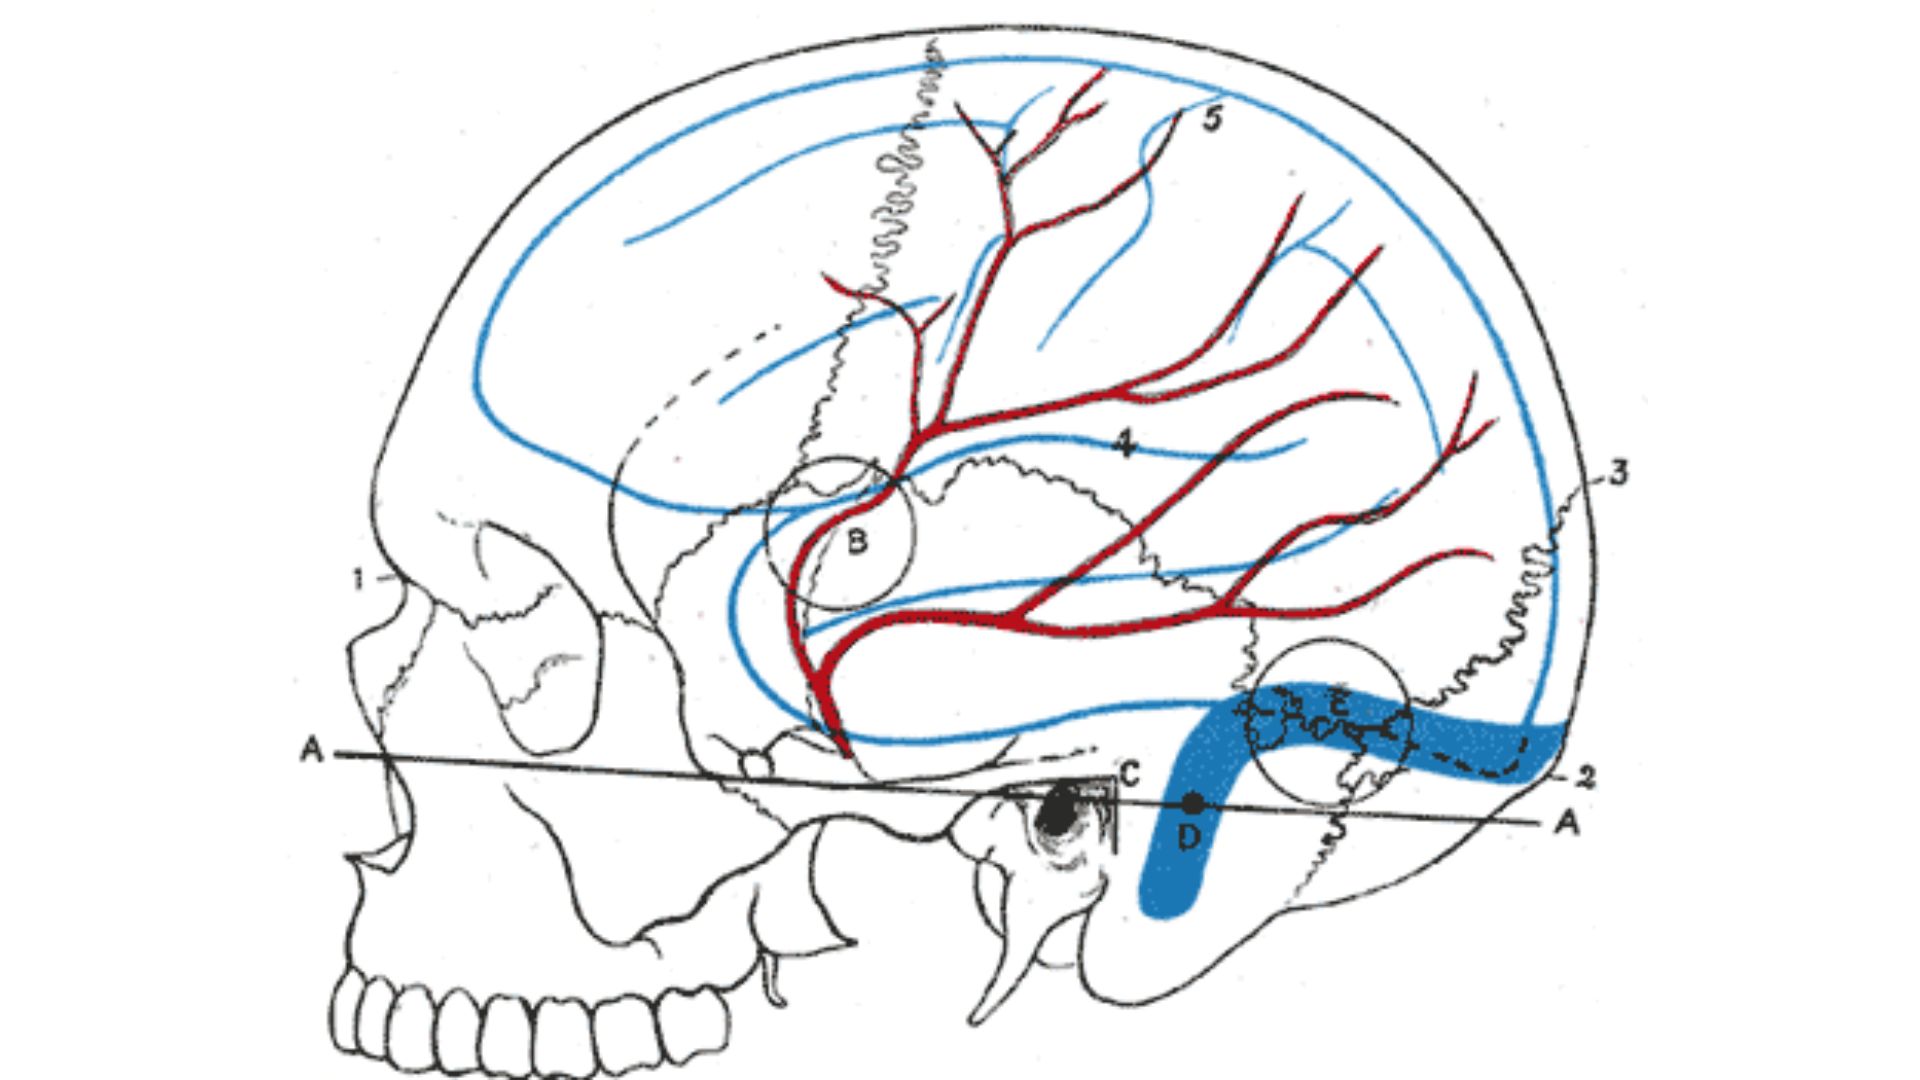

Laterale Ansicht des Schädels mit Lagebeziehung der A. meningea media (rot) zur Schädeloberfläche. Die Arterie verläuft zwischen Schläfenbein (Os temporale) und Dura mater und ist durch Knochenfragmente bei Frakturen besonders gefährdet.

A. meningea media - Laterale Ansicht des Schädels mit Lagebeziehung der A. meningea media (rot) zur Schädeloberfläche. Die Arterie verläuft zwischen Schläfenbein (Os temporale) und Dura mater und ist durch Knochenfragmente bei Frakturen besonders gefährdet.

Carter, H. V. (1858). Relations of the brain and middle meningeal artery to the surface of the skull (A. meningea media, rot markiert). In H. Gray, Anatomy of the Human Body (1918). Bartleby.com. Wikimedia Commons. https://commons.wikimedia.org/wiki/File:Gray1198.png

CC0 1.0

Ihr seid sicher auch bei den Arterien schon in manchen unserer Merkbilder Aa. meningeae oder Rr. meningei begegnet. Auch diese beziehen sich allesamt lediglich auf die Dura mater. Blutversorgt sind zwar natürlich alle drei Hirnhäute. Allerdings sind die Arterien der Dura mater makroskopisch gut zu sehen. Klinisch relevant ist v.a. die A. meningea media, die oft der Übeltäter ist bei Epiduralhämatomen. Es gibt aber noch weitere Meningealäste.